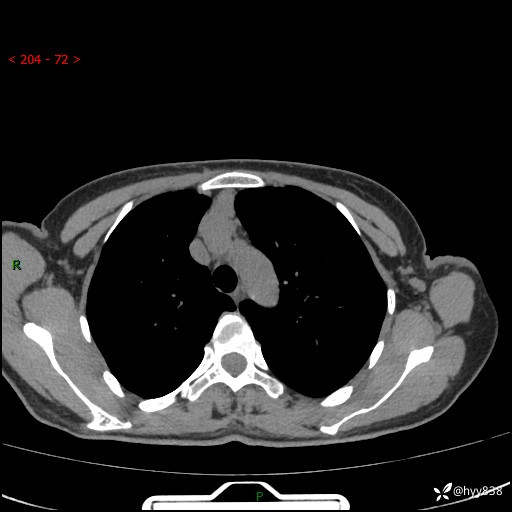

胸部CT平扫